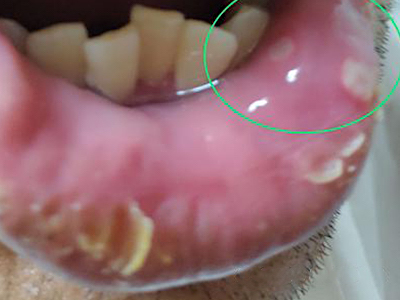

梅毒黏膜斑是二期梅毒最常见的口腔损害。可发生在口腔黏膜的任何部位,以唇黏膜最多见,其次为软腭、舌背、舌底等部位。损害呈灰白色、光亮而微隆的斑块,圆形或椭圆形,直径约1cm,边界清楚。易发生糜烂或浅表溃疡,表面覆盖灰白色假膜,周围有红晕。黏膜斑常为多个,内含有大量梅毒螺旋体。